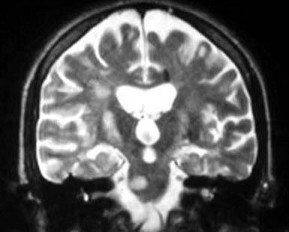

患者,女性,30岁,3年前因为双下肢麻木无力,治疗3周后症状消失。1年前右眼视力下降,未经治疗2周后好转。近1周出现走路不稳、复视。MRI表现如图。

A.右侧视神经炎

B.脊髓炎

C.脑干脑炎

D.多发性硬化

E.视神经脊髓炎